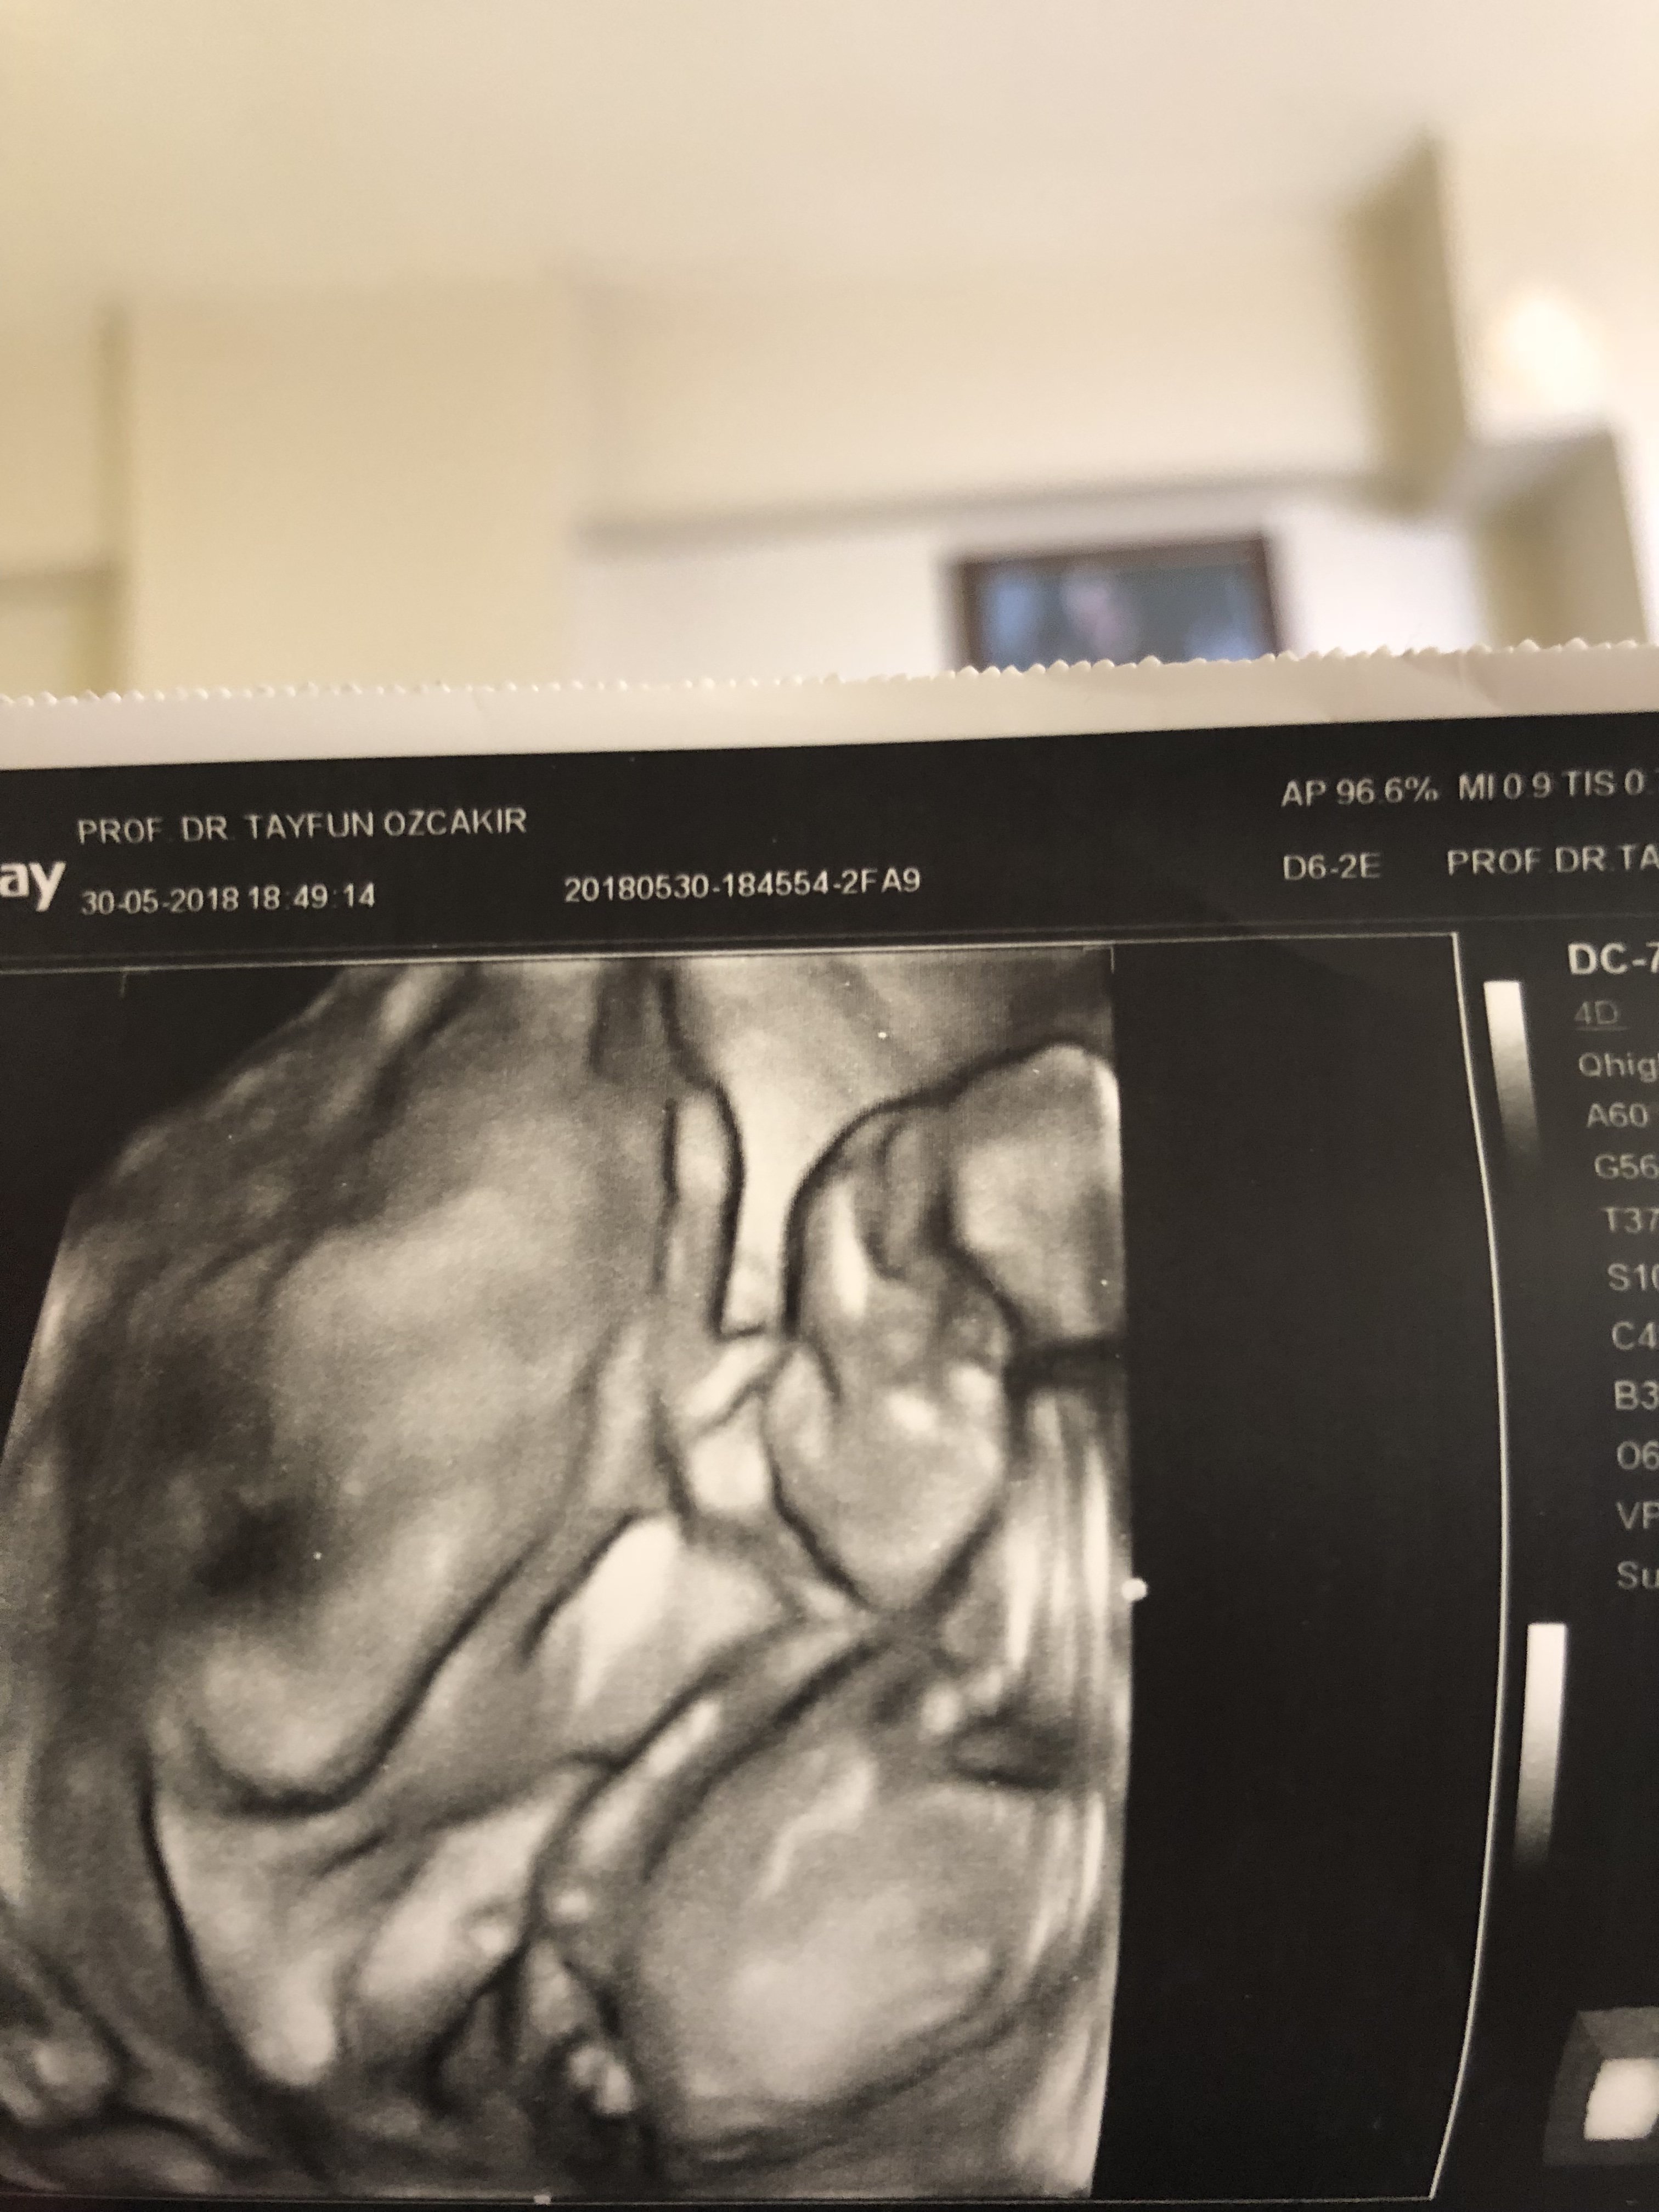

Merhaba, benim fotoğrafımı da yorumlayabilir misiniz rica etsem..

Merhaba, görseliniz pek net değil bebeğinizin cinsiyeti kıza benziyor .Hatırlatma yapalım bebeğinizin cinsiyetini net olarak 17-18-20. haftada öğrenebilirsiniz. Öncesi yapılan tahminler yanıltabiliyor.